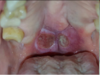

Which systemic disease manifests like this?

Crohn Disease

- Patients can also get angular cheilitis

- Above the Linear ulceration, can see a flap like structure which is the hyperplastic margin